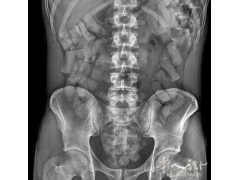

(组图)米兰警方查获一名男子体内藏毒 共收缴毒品730克